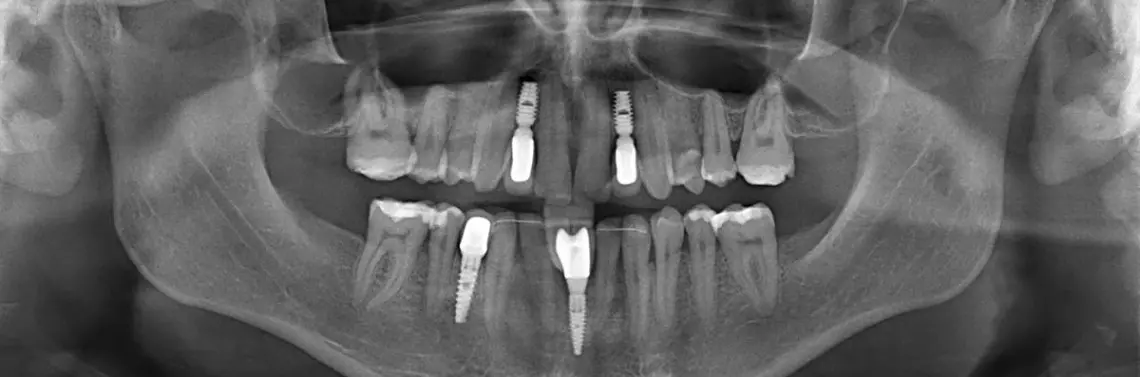

Mianem hipodoncji określa się zwykle wrodzony brak jednego bądź kilku zębów, co należy do częstych wad rozwojowych uzębienia. Może występować sporadycznie lub być dziedziczny. Często współistnieje z innymi nieprawidłowościami zębowymi, takimi jak zaburzenia morfologii, zmiany położenia zębów, opóźnienie ząbkowania. W naszym przypadku był to izolowany brak zębów (zdj. 1, 2, 3, 4) oraz przetrwałe siekacze dolne mleczne przy braku zawiązków zębów stałych.

Zdjęcie pantomograficzne wykazało wrodzony brak zębów 12, 22, 41, 31 i 44 oraz przestrzenie pomiędzy innymi zębami. Nieobecne są również drugie i trzecie trzonowce górne i dolne (zdj. 1).